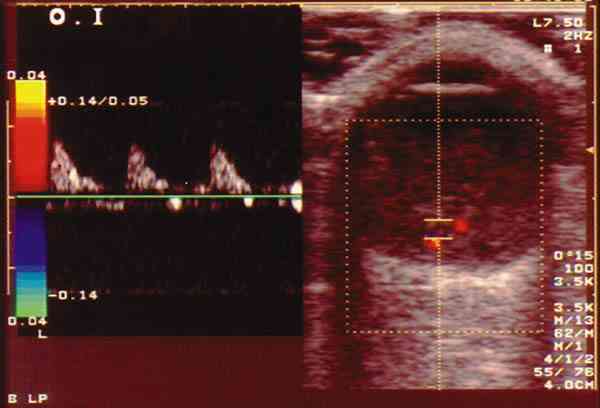

Figura 6. RB con extensa calcificación. Doppler color: registro

arterial en área no calcificada.

Figura 7. RB con extensa calcificación. Doppler color: registro